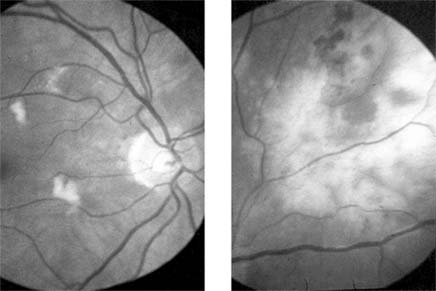

Figure 15-17

Figure 15-17: Diabetic retinopathy stage I. Trypsin-digested whole mount showing microaneurysms of the retinal capillaries.

Figure 15-18

Figure 15-18: Diabetic retinopathy. Fluorescein angiogram shows earliest stage with microaneurysm in the macular region.

Figure 15-19

Figure 15-19: Diabetic retinopathy. Fluorescein angiogram shows florid retinopathy of diabetes with extensive areas of capillary closure, dilated capillaries with microaneurysms, and early new vessel formation at the optic disk.

Figure 15-20

Figure 15-20: Proliferative diabetic retinopathy. Fluorescein angiogram shows extensive growth of vessels into the vitreous with marked fluorescein leakage.